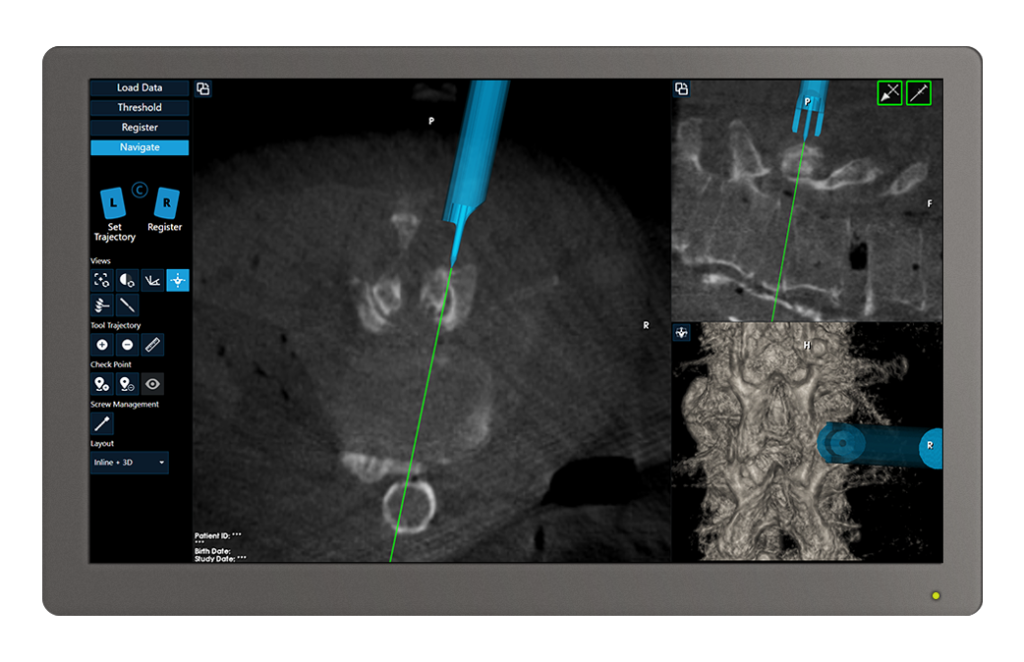

Seamless integration with 7D FLASH Navigation

Real-time tool projection provides a geometric representation of the Lumbar Inserter to help target the facet joints

The navigated Lumbar Inserter guides the Facet Drill during decortication

- Inserter forks center cannula on the joint line

- Enables equal decortication of superior and inferior facets

- Drill creates a contained defect within the inserter forks

- Inserter designed to control drill depth